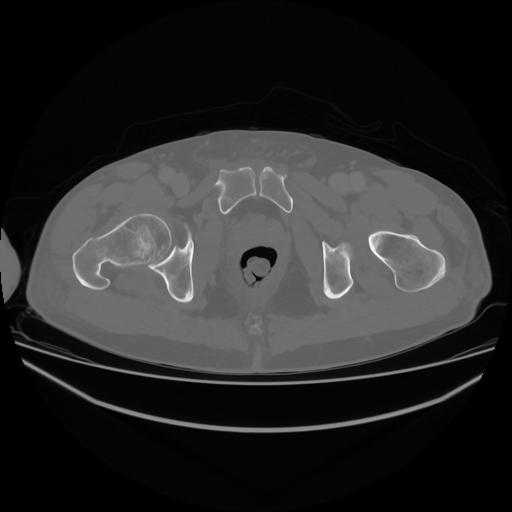

5 CUERPO,CE,Vol,1.0,CUERPO,,